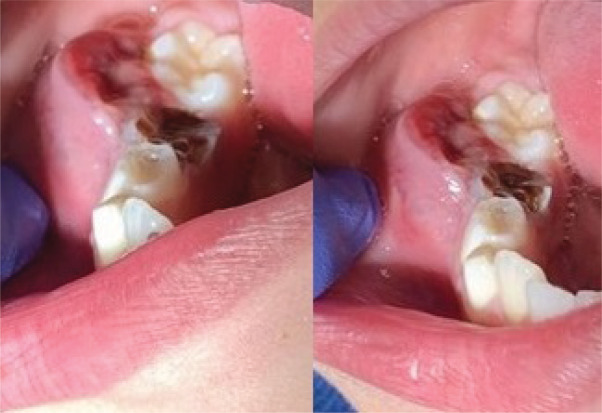

Teaching point: Peripheral giant cell granuloma (PGCG) is a common benign hyperplastic reactive lesion that originates from the soft tissues of the oral cavity and should be considered following a tooth extraction.

Abstract Image